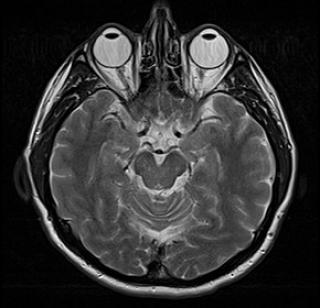

(Слева) Гемангиоперицитома околопозвоночной локализации. При КТ с контрастным усилением в аксиальной плоскости в подзатылочных мышцах интенсивно контрастируется образование, к которому подходит мощный сосудистый пучок.

(Справа) У этого же пациента при ангиографии в боковой проекции во время введения контрастного препарата в восходящую шейную артерию визуализируется типичное для гемангиоперицитомы обильное кровоснабжение. (Слева) При нативной КТ в аксиальной плоскости определяется очаг деструкции переднего кортикального слоя правой подвздошной кости. Мягкотканное образование в подвздошно-поясничной мышце едва заметно.